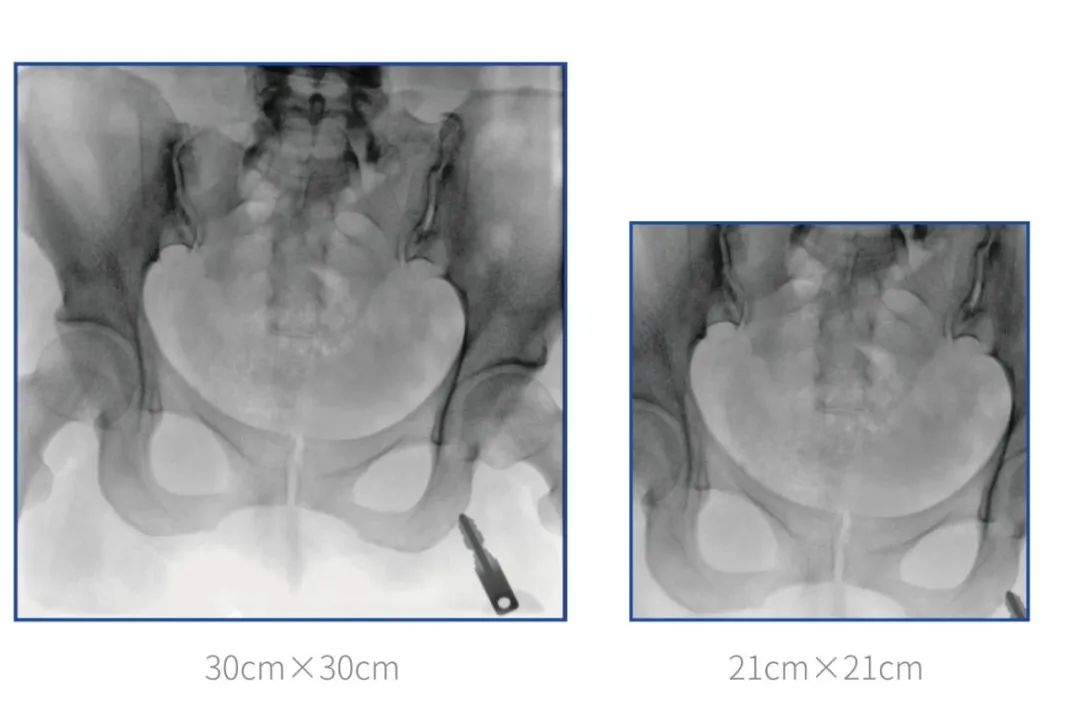

大尺寸平板C形臂 提供更多圖像細節(jié)

普愛醫(yī)療堅持自主研發(fā)、持續(xù)創(chuàng)新,從臨床需求出發(fā),推出了大視野,能夠呈現更多圖像細節(jié)的大平板一體式C形臂。大平板一體式C形臂配置30cm×30cm平板探測器,對于諸如骨盆雙側骨折類型手術或骨盆后環(huán)內固定術具有應用優(yōu)勢,一次曝光可獲取全部骨折部位影像,可簡化曝光流程,提高手術效率!